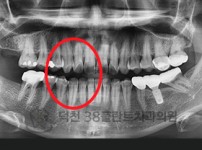

치료전후